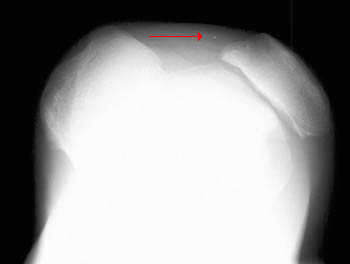

Lateral Patellar Dislocation

• Most dislocations of the patella are in the lateral direction.

• Diagnosis is easily made from standard radiographic examination of the knee.

Sunrise view of the knee